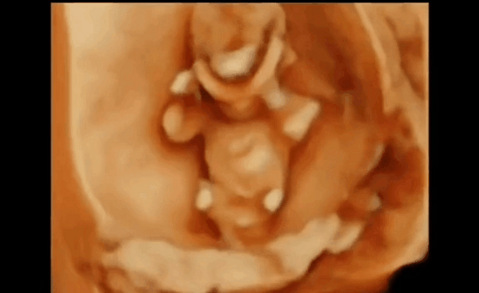

据说爸爸妈妈吵架的时候,肚子里宝宝的反应是这样的……

据说爸爸妈妈吵架的时候,肚子里宝宝的反应是这样的……我就想问问,看完以后,爸爸妈妈们还会不会再吵架? 请记住,不光是在怀孕期间,哪怕是在孩子出生后,上幼儿园、小学、初中、高中,也一定不要当着孩子的面吵架,因为看到、听到爸爸妈妈吵架,孩子们内心的反应都是一样的……